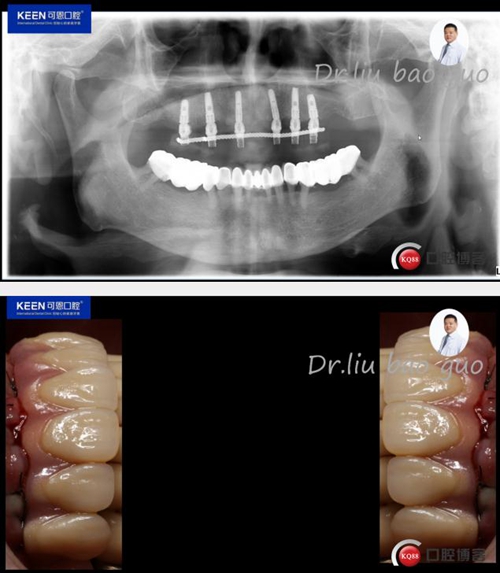

術(shù)后照片

種植后開(kāi)始進(jìn)行取模,制作義齒

義齒試戴及戴入后照片